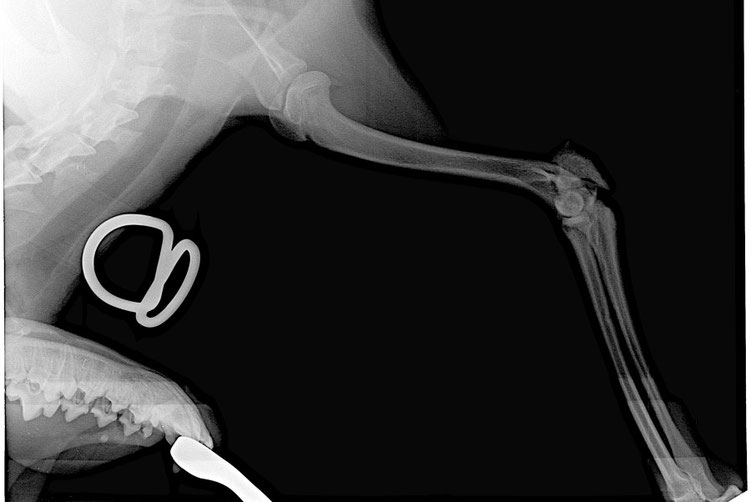

Selbstverständlich wurde das Vorderbein sofort geröntgt und glücklicherweise war das Bein nicht gebrochen.

Beim einem zweiten Röntgen wurde dann aber leider eine Fraktur des Oberschenkelknochens der Hinterbeine festgestellt.